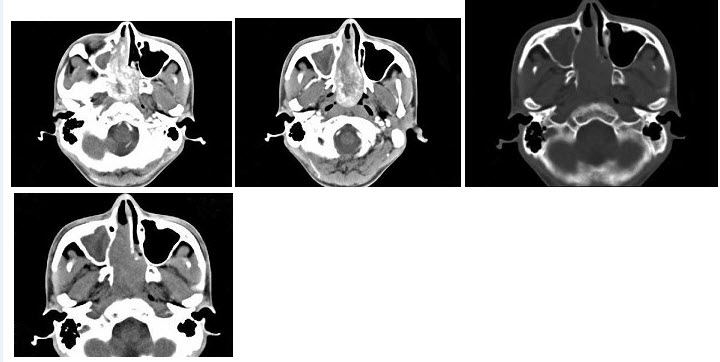

10、单项选择题

这个急诊患者剧烈上腹痛,结合图像,最可能的诊断是()

因静脉吸毒染上艾滋病的患者,如图所示,最可能的诊断是()

C.肌肉梗死

E.以上都不是

16、多项选择题 脊椎退行性变的CT征象包括()